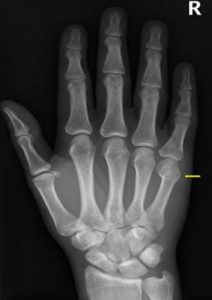

U heeft een breuk in het vijfde middenhandsbeentje (metacarpalia). De breuk zit in de buurt van de knokkel van uw pink. We behandelen deze breuk met tape en drukverband.